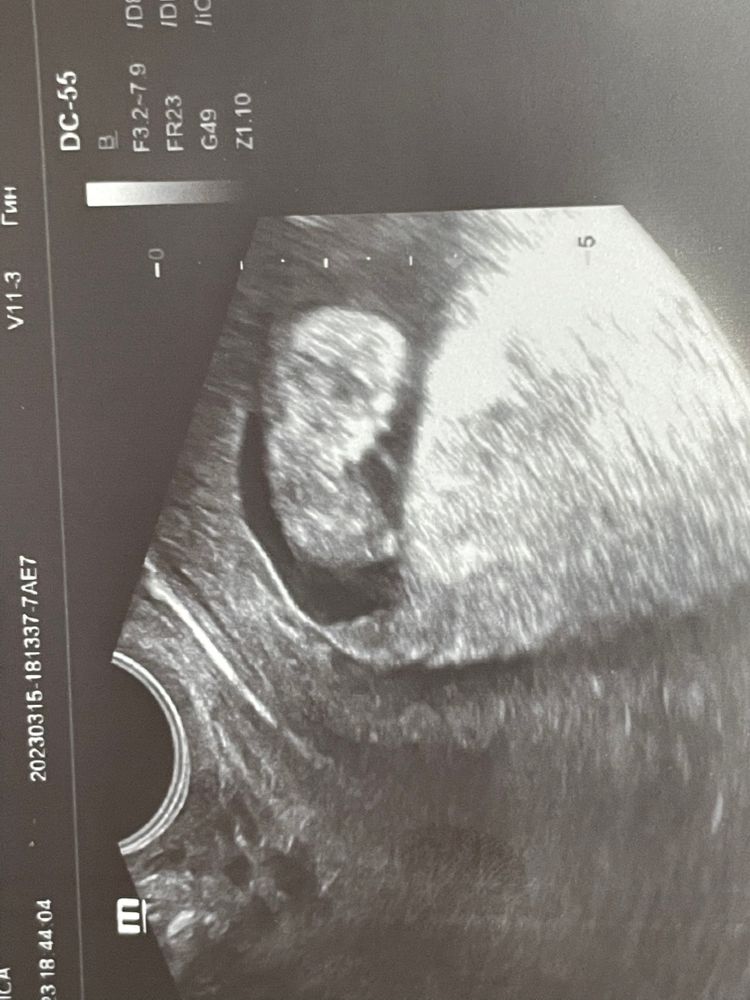

Пупсик такой 🥰